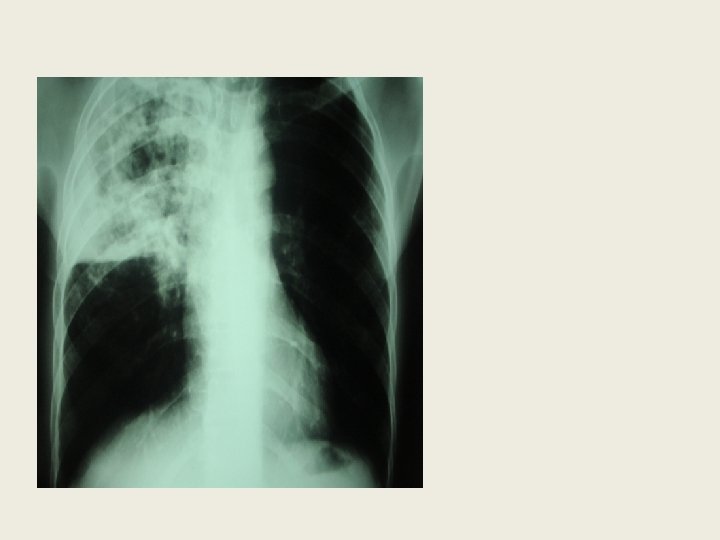

2. 2. Stade avancé( suite) • La bactériologie est souvent négative: recherche répétée et sur prélèvements divers • Intérêt du test Gen. Expert • Mise en culture sur le milieu de Loewen Stein Jansen+++ • Signes radiologiques souvent atypiques: ü Radiographie pulmonaire normale ü Opacités nodulaires ou réticulo nodulaires bilatérales et diffuses

2. 2. Stade avancé(suite) ü Atteinte des lobes inférieurs des poumons par des opacités parenchymateuses ü Rareté des cavernes et lorsque elles sont présentes, elles sont localisées au niveau des bases ü Pleurésies plus fréquentes